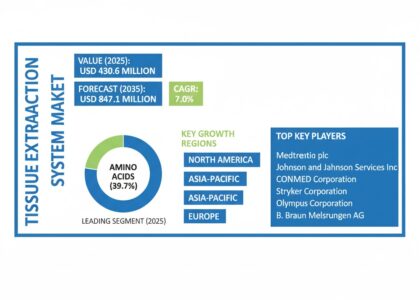

The global Tissue Extraction System Market is set for remarkable growth, with its value projected